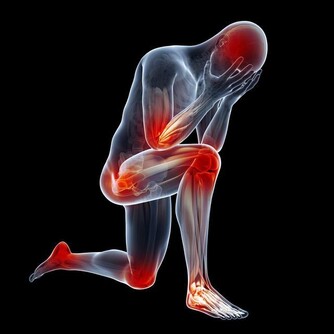

但其實我們的身上沒有一個部位是沒有用的,首先肛門的作用就有排氣,在日常生活中,無論是吃飯還是說話時,都會導致一些氣體進入到食道中,這時人體就會感到胃脹不舒服的感覺,要想排出就要通過肛門。

其次,排便可以說是我們每天都要做的事了,雖然很麻煩但是幾天不排我們還會很難受,我們體內的垃圾和毒素都要通過肛門排出,如果這些東西不排出就會導致肥胖,小肚子變大,甚至腸胃疾病。

最後肛門也有這保護腸胃的功能,很多人可能有些納悶肛門跟腸胃有什麼關係,其實肛門和我們的腸胃是連著的,也在為我們的腸胃阻擋一些外來細菌,因此如果肛門不及時清潔產生了細菌,久而久之就會導致細菌進入到腸道內部,引起腸道疾病。

1、痔瘡

相信大家都聽說過痔瘡,但卻不知道痔瘡是怎麼形成的,痔瘡形成的因素有很多,一方面是飲食和不健康的排便,還有一方面就是衛生的原因。

我們都知道這個部位有很多的褶皺,最容易殘存一些臟東西,比如糞便,長時間的不清潔,這其中的細菌會在肛門處肆意的繁衍,最終形成痔瘡,出現便血,並且會有明顯的疼痛感,嚴重的情況可能會出現肛門脫出的情況。

2、肛門膿腫

就像文中的小剛一樣,這是一種急性感染類的疾病,主要的病因是就細菌引起的,通常會出現在20歲到40歲的男性身上,患病後肛門的部位會感覺到疼痛和灼燒感,並且會有明顯的腫脹。嚴重的情況還會出現肛周的分泌物。甚至肛門周圍皮膚潰爛。

3、婦科疾病

對於女性來說肛門的清潔也是尤其重要的,一些女性只注重尿道的清潔,從而忽略了肛門的清潔,要知道這兩個部位離的比較近,其中的細菌也會互相傳染,因此,女性肛門的衛生也要格外注意,如果不經常清潔會導致女性產生婦科疾病。 文章來源: /c/user/token/MS4wLjABAAAAAAQu9_Gg04N0izpyNsAFJwcluMgUX-WfEtQfY0m4D-U/?source=tuwen_detail